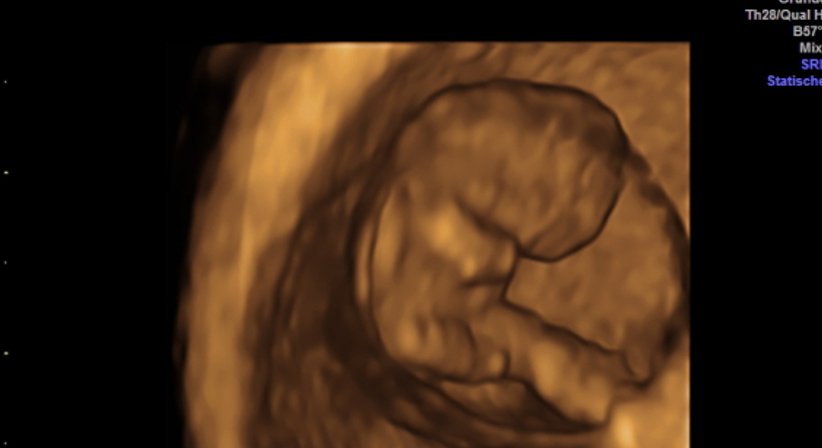

Wir verfügen seit 2015 über ein extrem hochwertiges Ultraschallgerät, das neben einer sehr guten Bildauflösung Techniken wie 3D Ultraschall, 4D Ultraschall und verbesserten Dopplerultraschall bietet. Ich selbst bin für diese Techniken sowie die Nackenfaltenmessungen (in der Frühschwangerschaft) zertifiziert. Bilder und Filme werden auf Wunsch auf einen USB-stick gespielt, sodass man diese mit nach Hause nehmen kann.

Mit verschiedenen Methoden können wir heute beurteilen, ob während der Schwangerschaft mit Mutter und Kind alles in Ordnung ist, oder ob Risiken vorliegen. Der Ultraschall hilft uns dabei als nahezu einzige Methode, das ungeborene Kind in der Gebärmutter direkt sichtbar zu machen.